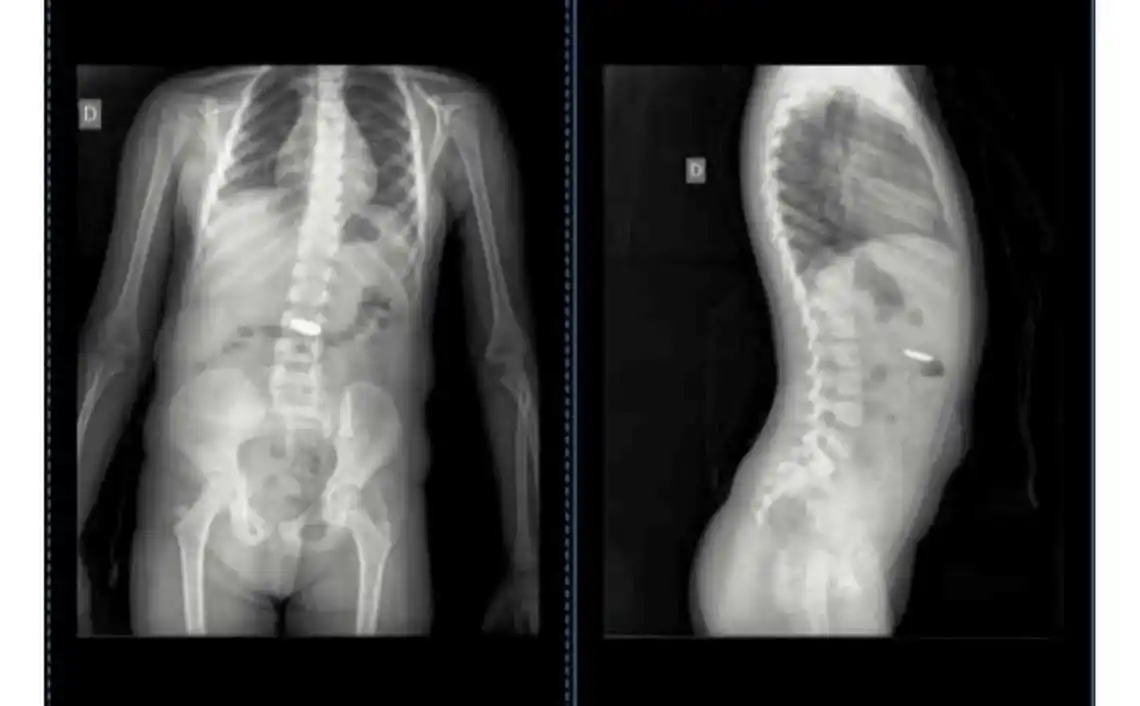

“Siete médicos en Chascomús vieron las imágenes de las radiografías que le hicimos a Isabella por el tema de la pila ‘botón’ que se tragó. ¡¡Sí, siete!! Cuatro en la Guardia y 3 por mensaje, solo uno, al que le pasé por mensaje ayer, supo ver lo que pasaba”, indicó la madre de Isabella en un posteo realizado en la madrugada de este lunes en su cuenta de Facebook.

La nena, que se había tragado la pila “botón” el jueves pasado, fue llevada al Hospital de Niños de La Plata, donde le realizaron una endoscopia y le pudieron extraer la pila. La madre dijo que “por suerte decidí hacerle caso” al Dr. Jorge Ortale que detectó la presencia del elemento extraño en la radiografía de su hija.

“Pregunto ahora: ¿de siete sólo uno vio lo que pasaba? ¿Y si esa pila seguía ahí y provocaba un mal mayor a mi hija? Desde el jueves 22/6 mi hija tenía esa pila en su estómago. Gracias Doc. Jorge Ortale, usted sí supo ver lo que pasaba”, destacó Ganuza.